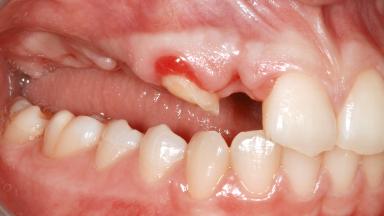

Ridge Preservation and Implant Placement for a Fixed Dental Prosthesis After a Car Accident

It is well known to clinicians that any removal of teeth will, over time, cause the dimensions of the alveolar ridge to be reduced by resorption of the bundle bone and by changes related to external modeling. This development is particularly evident in the crestal region with its thin buccal bone that consists of bundle bone almost entirely. The facial bone will rapidly resorb as blood supply from the periodontal ligament gets disrupted (Araújo and Lindhe 2005). There is no reason why traumatic tooth loss should not have the same consequences. It takes more than achieving implant osseointegration for a treatment outcome to be considered successful. No deficiency of bone or soft tissue is acceptable when an ideal esthetic outcome is the goal. Several articles (Sanz and coworkers 2011; Vignoletti and coworkers 2011) have reported on techniques of improving the alveolar ridge for implant treatment, notably focusing on protecting tissues from resorption.

Soft Tissue Anatomy Intact Defective

Bone Volume Horizontally and vertically sufficient Horizontally deficient Deficient vertically or deficient vertically AND horizontally